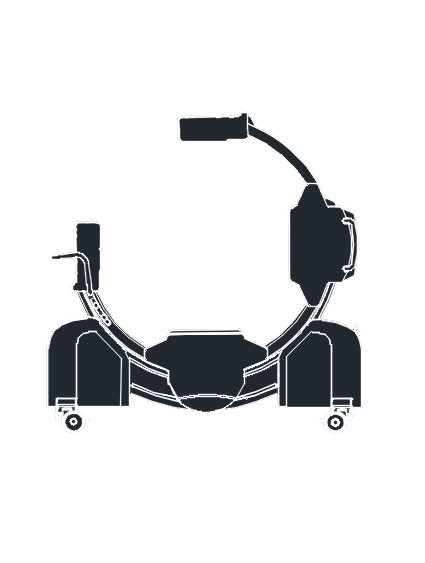

KXR3000 is designed to improve efficiency and safety in orthopedic, spine, neurosurgery, and trauma procedures.

Dual-plane real-time views enable rapid positioning between AP and lateral views without moving the equipment.

A-Beam® technology delivers superior accuracy, greatly reducing the likelihood of revision surgeries.

Eliminates the need to reposition detectors during surgery, reducing interference with the sterile field.